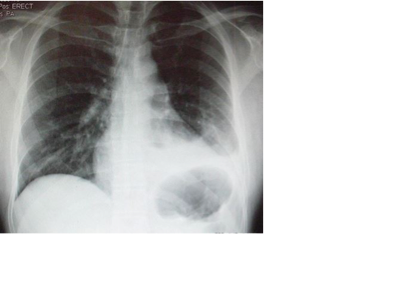

The most common cause of hemopneumothorax is chest trauma. Some other causes are gunshots or knife wounds to the chest, rib fracture, or certain medical procedures.

A sports injury that can cause hemopneumothorax might be a hard hit to the chest area.

Etiology